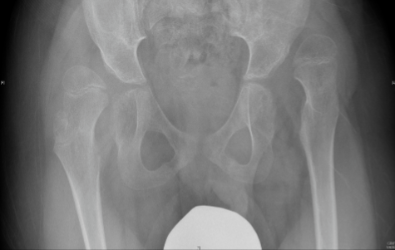

Children with cerebral palsy which are non-walkers need to be screened for hip dislocation. Hip dislocation is common in children with cerebral palsy that are restricted in wheelchairs. Prevention of hip dislocation is important because it causes severe pain, lower limb deformities and scoliosis. In many countries universal pre-symptomatic hip screening is performed which has resulted in significant reduction in the number of hip dislocations. It is therefore recommended that regular clinical and radiological assessment is performed in children with cerebral palsy that are not able to walk. In order to avoid hip dislocation the doctor depending on clinical and radiological assessment in each patient can recommend physiotherapy or orthotic treatment, Botox injections or surgical intervention in order to release soft tissues. However, when hip dislocation results in femoral head uncovering of more than 40%, surgical intervention is required in order to reduce the hip, usually with a femoral and/or a pelvic osteotomy.

The x-rays below are of a child with cerebral palsy (a non-walker) with bilateral hip dislocation and severe pain. The patient underwent bilateral femoral and pelvic osteotomies in order to reduce the hips.

Pre-operative